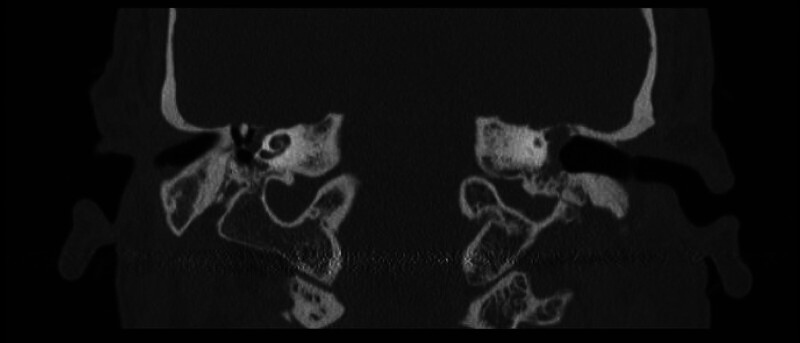

Objective: Occasionally, repair of tegmen defects can be complicated by the ossicular chain protruding above the floor of the middle fossa, which traditionally requires disarticulation and reconstruction of the ossicles to manage. This manuscript describes modifications of previously described techniques to address this surgical problem.

Participants: In this case series we present three patients with tegmen defect and encephalocele where the ossicles protruded over the floor of the middle fossa. In one instance, a "manhole cover" was created by concentrically layering hydroxyapatite cement around the tegmen defect and placing a piece of calvarium harvested from the bone flap over the defect. In another case, a "bony igloo" was drilled into harvested bone flap and placed over the defect, effectively creating a neo-epitympanum.

Conclusions: The "manhole cover" and "bony igloo" techniques are pragmatic solutions to this rare but complex surgical problem.